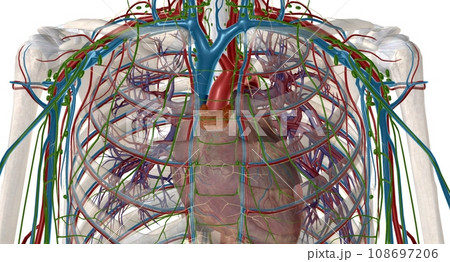

イラスト素材: The thymus is an important p of the body's immune system.

The thymus is an important p of the body's...[108697206]のイラスト素材は、器官、血管、人体のタグが含まれています。この素材はgoldpic34さん(No.2485601)の作品です。SサイズからXLサイズまで、¥550からご購入いただけます。無料の会員登録で、カンプ画像のダウンロードや画質の確認、検討中リストをご利用いただけます。 全て表示

The thymus is an important p of the body's immune system.